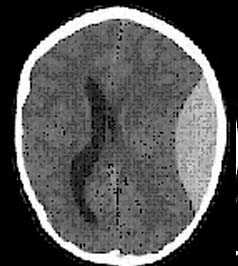

Применение компьютерной томографии в нейротравматологии существенно изменило представление о возможностях диагностики различных черепно-мозговых повреждений. КТ является в настоящий момент «золотым стандартом» - наиболее информативным методом обследования больных с черепно-мозговыми травмами и позволяет в самые короткие сроки судить о механизмах возникновения поражения мозга, его характере, распространенности, выраженности отека и дислокации мозга, а также динамике этих изменений.

- выявить наличие внутричерепной гематомы (её характер, локализацию, размеры),

- определить степень сдавления или дислокации головного мозга объемным процессом,

- выявить внутрижелудочковую гематому,